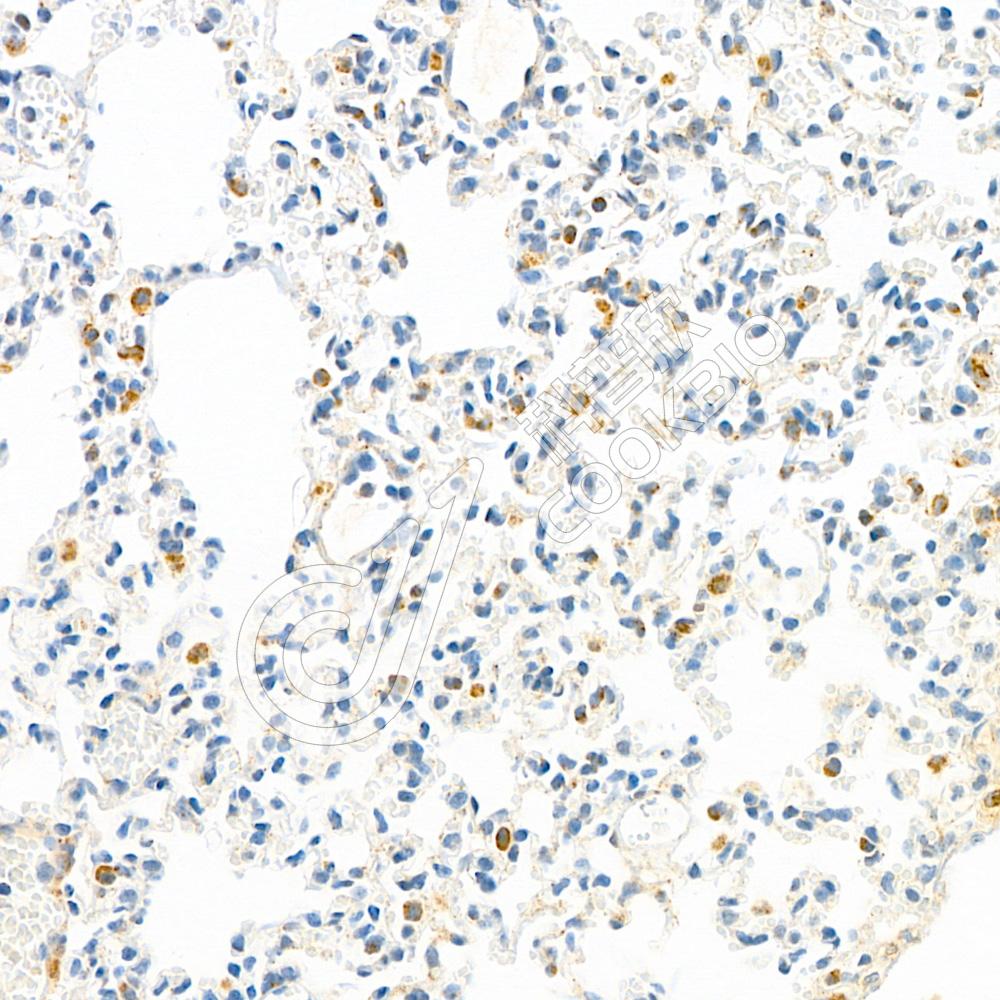

IHC检测PSAP蛋白(货号 K1333516).

样品: 小鼠肺, 4%多聚甲醛 (货号KSG1101) 固定12-24小时.

抗原修复: 柠檬酸抗原修复液(干粉, pH 6.0) (KSG1201), 98℃, 20分钟.

—抗: 1: 1100稀释, 4℃ 孵育过夜.

二抗: S-vision免疫组化多聚二抗(山羊抗兔),即用型 (货号KB3906), 室温孵育20分钟.